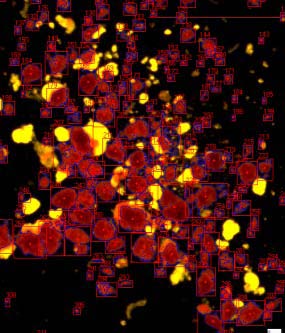

ICC4-230是胰島細(xì)胞自動化計(jì)數(shù)儀器:

2. 全新的暗場照明提高了小顆粒檢測、圖像分割的能力,并且可以計(jì)數(shù)純化的未染色樣本;

細(xì)胞自動檢測,SNR掃過RGB范圍后的閾值

先進(jìn)的自適應(yīng)分區(qū)算法